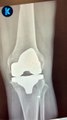

Joint injections of hyaluronic acid help to lubricate and cushion, but when you get the right molecular weight in high concentration, you can also achieve biosynthesis of endogenous hyaluronic acid, creating a healthier synovial fluid.